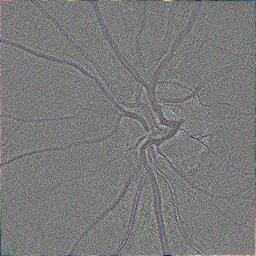

Modern deep neural networks struggle to transfer knowledge and generalize across diverse domains when deployed to real-world applications. Currently, domain generalization (DG) is introduced to learn a universal representation from multiple domains to improve the network generalization ability on unseen domains. However, previous DG methods only focus on the data-level consistency scheme without considering the synergistic regularization among different consistency schemes. In this paper, we present a novel Hierarchical Consistency framework for Domain Generalization (HCDG) by integrating Extrinsic Consistency and Intrinsic Consistency synergistically. Particularly, for the Extrinsic Consistency, we leverage the knowledge across multiple source domains to enforce data-level consistency. To better enhance such consistency, we design a novel Amplitude Gaussian-mixing strategy into Fourier-based data augmentation called DomainUp. For the Intrinsic Consistency, we perform task-level consistency for the same instance under the dual-task scenario. We evaluate the proposed HCDG framework on two medical image segmentation tasks, i.e., optic cup/disc segmentation on fundus images and prostate MRI segmentation. Extensive experimental results manifest the effectiveness and versatility of our HCDG framework.